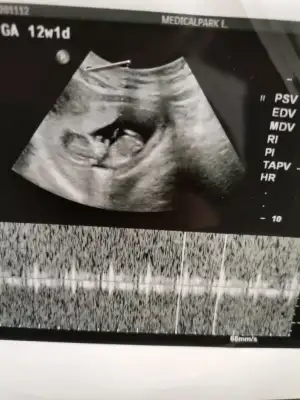

Merhabaaalarrr Lütfen bana da bakabilirmiainiz Sevgili Ikra Meyra🙏